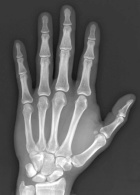

F.W. - 33 year old man with a recent discovery of a painful mass in his left hand

Zoom image: Radiological image Radiological image.